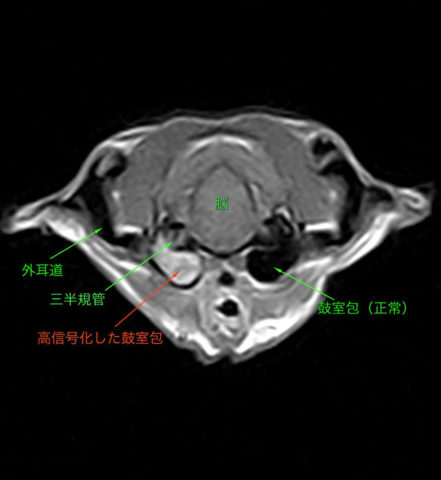

13歳 猫

急性の斜頸とふらつき

MRI(左図)にて右中・内耳領域の高信号化あり

右側の中・内耳炎と診断

貯留液の採取および洗浄のために鼓室包切開術を実施

膿が採取されたため、薬剤感受性試験を行い抗生剤による治療を行い、その後症状良化